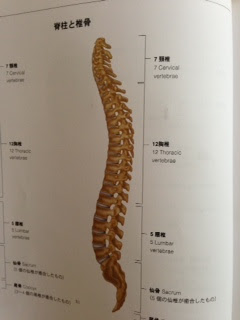

骨盤の質問

「出産時は、おっしゃるとおりに、骨盤の間接が緩んで調整します。しかし、骨盤内底筋群や、腰周りや、大腿内側の緊張ですぐに骨盤の位置は変わってしまいます。基本的な骨盤の位置は、ASISが開いていて、腰が反って生理的な脊柱の湾曲が理想です。」

とのことでした。なので、脊柱がいい位置ならいい骨盤の位置ということです。

バレエをされてる方からの質問だったのですが、この脊柱、バレエダンス系の方は脊柱を伸ばそうとするあまり、頚椎、腰椎のカーブがあまりない傾向にあると思います。骨盤と近い、腰椎を伸ばしすぎると、骨盤がやや後傾します。そうすると、骨盤や腰椎の本来の位置と違ってくる可能性もあります。ターンアウト(脚を股関節から外側に回すこと・アンディオール)も骨盤を後傾させてしまいますからますます背骨のカーブをなくしてしまいます。

実は、私も新体操、ダンス出身者のため、脊柱をまっすぐ伸ばし続けてきたため、背骨の自然なS字のカーブがおかしくなっています。

レントゲン写真は私が首を痛めた時のものです。なんと頚椎(首の骨)のカーブがまっすぐどころか反対のカーブでした。ヨガのイントラをしていながらお恥ずかしいです。

レントゲンも骨の絵(骨格筋ハンドブック 南江堂より)も左側を見て立っている脊柱です。骨の絵では上から7つのところ頸椎とかいてある部分になります。それで、首を痛めやすいとお医者さんに言われ、思い当たるものがかなりありました。

頸椎のカーブがおかしいのは自分では気づきませんでした。人のばかり気にして自分は自然なS字のカーブがないなんて笑ってしまいます。客観的に見るっていいですね。